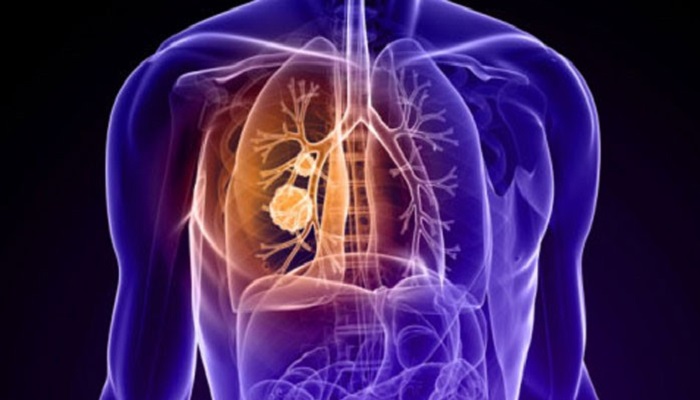

ابتلای روزانه ۳۰ نفر به سل در کشور/ تشخیص سل به دلیل تشابه علائم تنفسی با کرونا سختتر شده است

مدیر گروه بیماریهای واگیر دانشگاه علوم پزشکی کرمانشاه تصریح کرد: سل پرچمدار مرگ از بیماریهای عفونی بوده و پس از کرونا تا مدتها باقی میماند.

وی با بیان اینکه تشابه علائم تنفسی سل با کرونا کار تشخیص سل را سختتر کرده است، گفت: روزانه ۳۰ مورد جدید سل در کشور بروز کرده و از این تعداد سه نفر بر اثر ابتلا به سل جان خود را از دست میدهند.